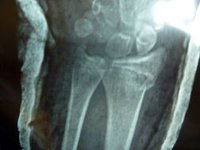

手腕骨折在日常生活中較為常見,受傷者中以老年人居多,大部分患者是因為跌倒後手掌著地所致。骨折多發生在橈骨遠端近關節2cm處,臨床上稱為柯力氏骨折。如未得到及時有效的治療,患者腕關節將遺有關節畸形、關節活動功能受限,以及關節疼痛等症狀,常給患者的日常生活帶來諸多不便。因此,診治時必須做到正確的復位、良好的固定。

手腕骨折治療方法有保守治療和手術治療兩種。保守治療主要採取手法復位、小夾板或石膏托外固定。雖然保守治療可以做到早期的關節功能鍛鍊,但由於保守治療有骨折固定不牢固之慮,骨折可能發生再移位,而導致治療的失敗。手術治療主要是採取手術切開復位,並行鋼板等內固定。手術切開復位可以做堅強的內固定。